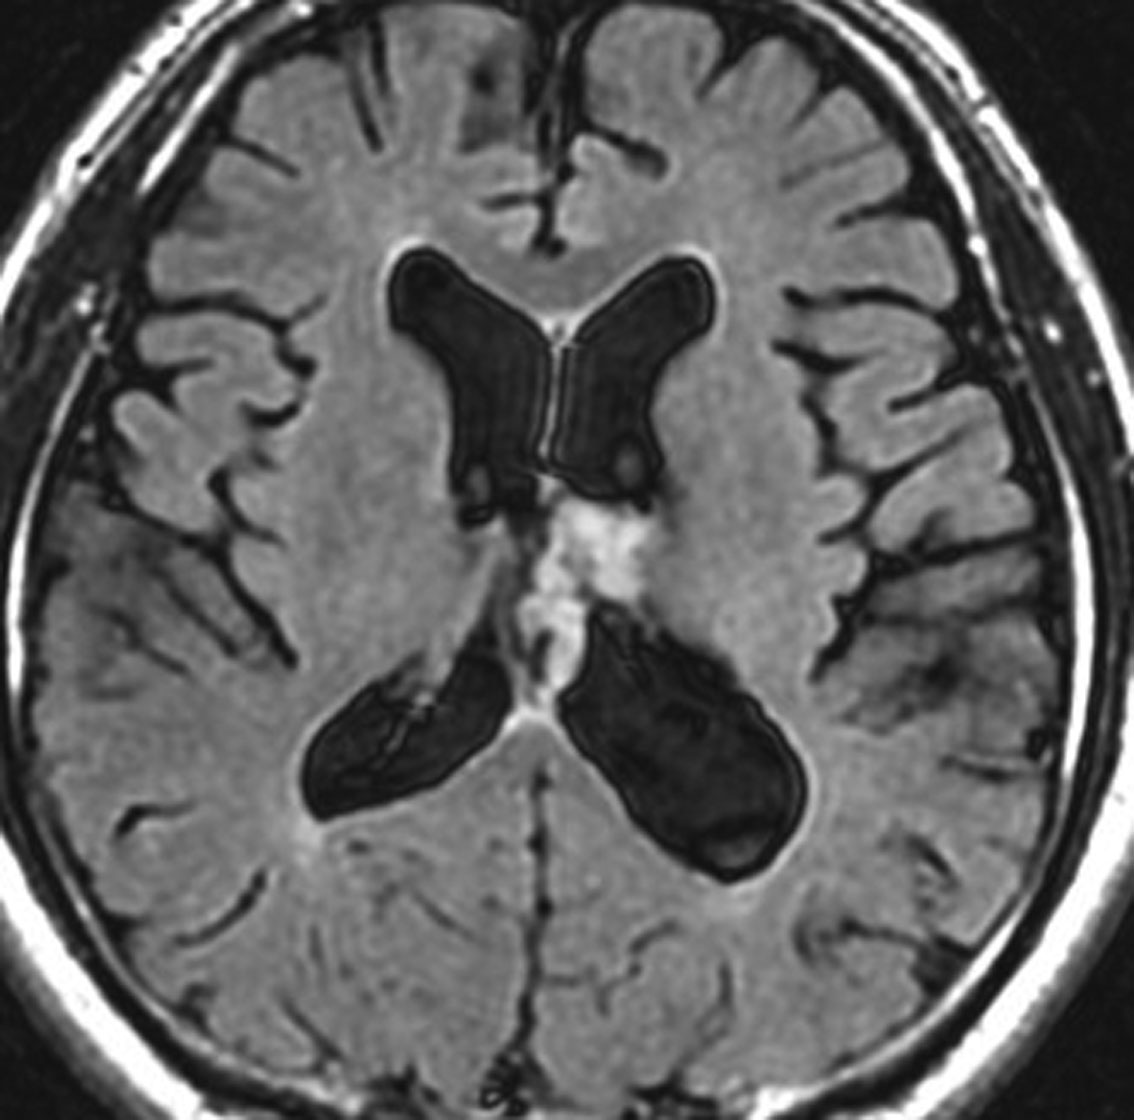

10年観察してもあまり変わらない,数が増えることがある

2012年に偶然発見され,その後,10年の経過観察されました。

2022年のものです,透明中核から出たものは少し大きくなっています。他にも数個の小さな腫瘍が脳室上壁にあるのですが,なにもしないでほっておきます。